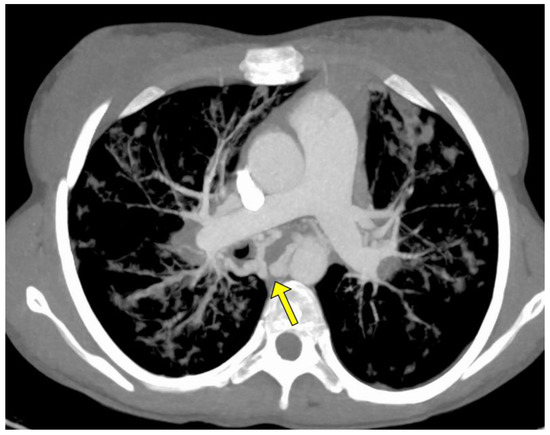

| Procedures | ID Pz. | Vessel Type Treated with BAE | Caliber of Treated Vessel (mm) Pre-Procedure CT | Untreated Vessel Size (mm) Pre-Procedure CT | ∆ Significant Caliber between Left and Right? | Arterial Vessel Studied in Diagnostic Angiography |

| 1 | 1 | Left | 5 | 2 | Yes | Bronchial left |

| 2 | 1 | Left | 5 | 3 | Yes | Bronchial left |

| 3 | 2 | Right | 6 | 2 | Yes | Bronchial right |

| 4 | 2 | Left + Right | 7.5 | 3.5 | Yes | Bronchial right and left * |

| 5 | 3 | Right | 6 | 3.5 | Yes | Bronchial right |

| 6 | 4 | Right | 7 | 6 | No | Bronchial right and left |

| 7 | 5 | Right | 3.5 | 3.5 | No | Bronchial right and left |

| 8 | 6 | Right | 8 | 5 | Yes | Bronchial right |

| 9 | 7 | Right | 5 | 2 | Yes | Bronchial right |

| 10 | 7 | Right | 5 | 2 | Yes | Bronchial right and left |

| 11 | 7 | Right | 5 | 2 | Yes | Bronchial right |

| 12 | 8 | Right | 3 | 2 | No | Bronchial right and left |

| 13 | 8 | Right | 4 | 2 | No | Bronchial right and left * |

| 14 | 9 | Left | 8 | 7 | No | Bronchial left * |

| 15 | 10 | Right | 7 | 1 | Yes | Bronchial right |

| 16 | 10 | Right | 7 | 1 | Yes | Bronchial right |

| 17 | 11 | Right | 5 | 3 | No | Bronchial right and left |

| 18 | 12 | Left | 7 | 4.5 | Yes | Mammary left |

| 19 | 13 | Right | 3.5 | 0.5 | Yes | Bronchial right |